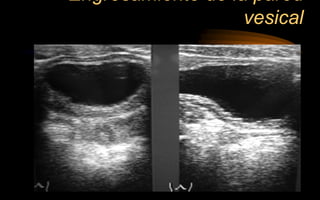

Engrosamiento de la pared

vesical

Engrosamiento por tumores

Engrosamiento de lapared vesical